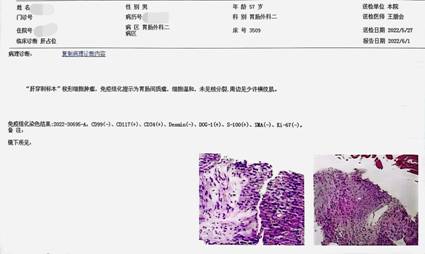

本来计划先完成超声定位下穿刺活组织病理检查,为下一步精准治疗做准备,却因为患者的极度恐惧心理而无法执行,至关重要的穿刺活检遇到了阻碍。这种情形下还是曹高健主任出马,经过推心置腹的耐心劝导,患者咬牙同意了。结果当然是可喜的,在我们超声影像科王朋会主任的高水平穿刺操作下,顺利获取了肿瘤组织,其病理报告与分子检测结果(图3),也证实了曹主任高侵袭性胃间质瘤的判断。于是我们邀请了肿瘤内科、放射影像科进行了多学科讨论(MDT),会诊结论:患者为胃间质瘤侵犯邻近多个器官,当前无手术根治机会,根据病理及分子检测结果一线推荐伊马替尼靶向治疗;若疗效显著或病灶稳定,可再次进行多学科讨论,评估联合手术切除的获益。有了明确的治疗方案,我们便开始让患者口服伊马替尼进行靶向治疗。

图3 肿瘤穿刺活检病理及免疫组化报告